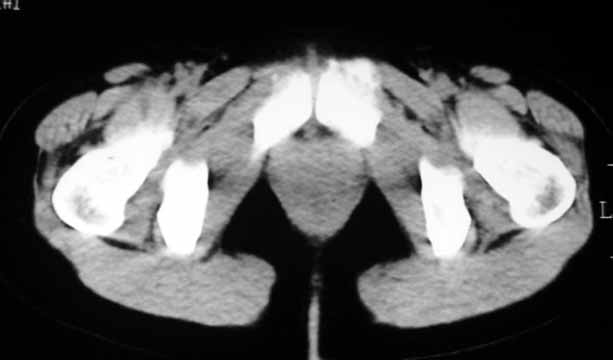

标题: CT8123:女46岁,左下腹胀痛不适1月,以前曾有月经过多史,现已 [打印本页]

标题: CT8123:女46岁,左下腹胀痛不适1月,以前曾有月经过多史,现已

子宫肌瘤,不强化不好说

考虑子宫们内膜癌并右侧腹股沟淋巴结转移

子宫增大密度较均匀,考虑子宫肌瘤,不强化不好说

考虑子宫肌瘤(变性)或子宫腺肌病,不排除内膜ca可能,不增强建议结合mri或b超检查。

子宫们内膜癌或子宫颈癌体部浸润并右侧腹股沟淋巴结转移

子宫增大密度较均匀,考虑子宫肌瘤可能性大,